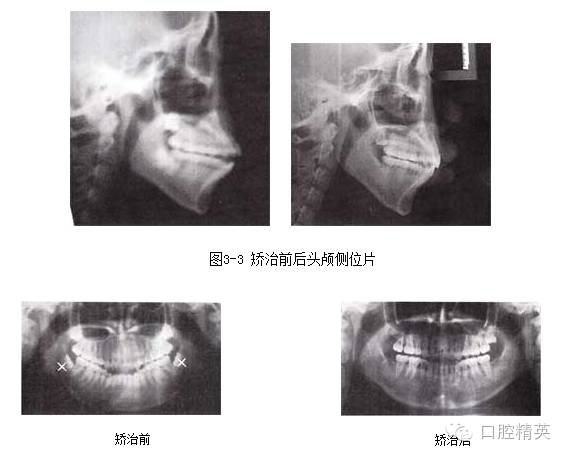

圖3-4 矯治前后全口曲面斷層片

檢查:恒牙列,雙側(cè)磨牙中性偏遠(yuǎn)中關(guān)系,11、12 、13 、21、22 、23中度開頜,上下頜牙列輕度擁擠。正面觀,面型左右對(duì)稱;側(cè)面觀,雙頜前突,明顯開唇露齒,下頜頦部發(fā)育不良致后縮。顳下頜關(guān)節(jié)無(wú)異常。

開頜且合并有一定程度的前突和擁擠病例,選擇拔牙矯治。在關(guān)閉間隙,內(nèi)收上下前牙的同時(shí)產(chǎn)生鐘擺效應(yīng),可以較好地糾正開頜。該病例磨牙偏遠(yuǎn)中關(guān)系,下頜選擇拔除雙側(cè)第二前磨牙有利于調(diào)整磨牙關(guān)系;而上頜拔牙則有利于更好地內(nèi)收上頜前牙。

4.阻生第三磨牙的拔除對(duì)于開頜的矯治效果及療效的穩(wěn)定十分關(guān)鍵。

5.開頜患者通常會(huì)伴有后牙的近中傾斜,MEAW技術(shù)的應(yīng)用可以壓低并直立磨牙,有利于開頜的矯治。在MEAW使用過(guò)程中,需要將第二磨牙納入矯治序列。同時(shí)強(qiáng)調(diào)在前牙區(qū)使用垂直牽引。